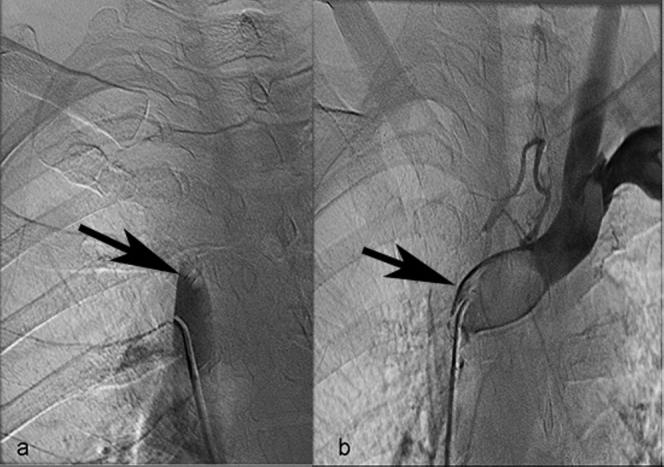

The current management of neoplastic obstruction, SVC, and brachiocephalic vein thrombosis, especially of SVC, is based on the combined use of interventional (endovascular thrombolysis or thrombectomy, stent placement) and noninterventional (radiation, chemotherapy) means of treatment. We present the case of a forty-year-old woman with SVC and left brachiocephalic vein thrombosis secondary to lymph node metastasis of non-small-cell lung cancer. A combination of rheolytic thrombectomy (Angiojet device) and stent placement was performed for both venous sites with complete technical success. We discuss the principles of percutaneous rheolytic thrombectomy, its effectiveness, and potential complications.

目前,对于肿瘤性上腔静脉(SVC)和头臂静脉血栓形成,尤其是SVC血栓形成的治疗,是基于介入(血管内溶栓或血栓切除术、支架置入)和非介入(放疗、化疗)治疗手段的联合应用。我们报告了一例40岁女性患者,其因非小细胞肺癌淋巴结转移继发SVC和左头臂静脉血栓形成。对两个静脉部位均进行了旋切血栓切除术(Angiojet装置)和支架置入术,技术上取得了完全成功。我们讨论了经皮旋切血栓切除术的原理、有效性及潜在并发症。